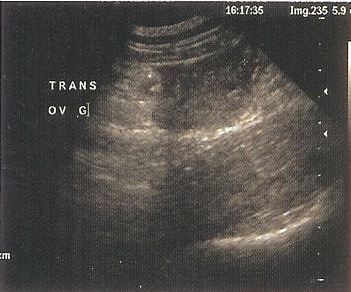

Ultraschalldiagnostik